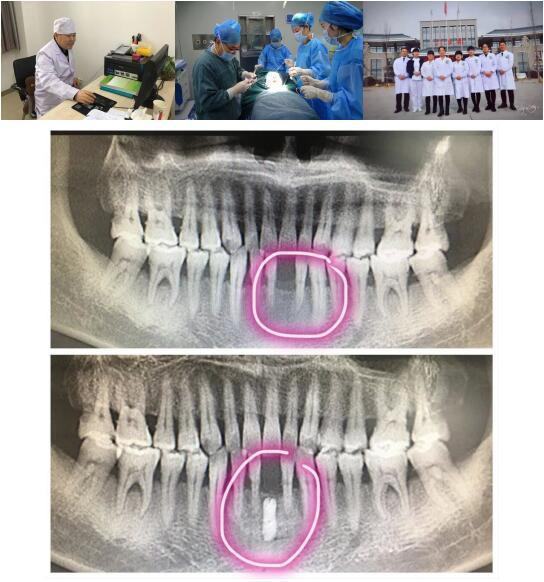

成人导航 高陵院区口腔科成功开展一例GBR引导骨再生技术种植牙